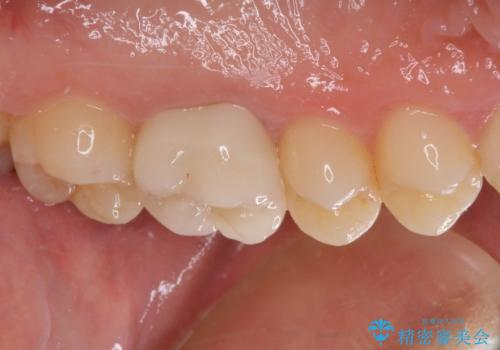

後日状態を確認したところ、残された神経に異常がなかったため、セラミッククラウンにて補綴治療を行いました。

セラミック治療の注意事項(リスク・副作用など)

- 天然歯を削ります

- 硬い素材は天然歯を傷つけてしまう場合があります

- かみ合わせや歯ぎしりが強すぎる方はセラミックが割れてしまう可能性があります

- 自費診療(保険適用外治療)となります